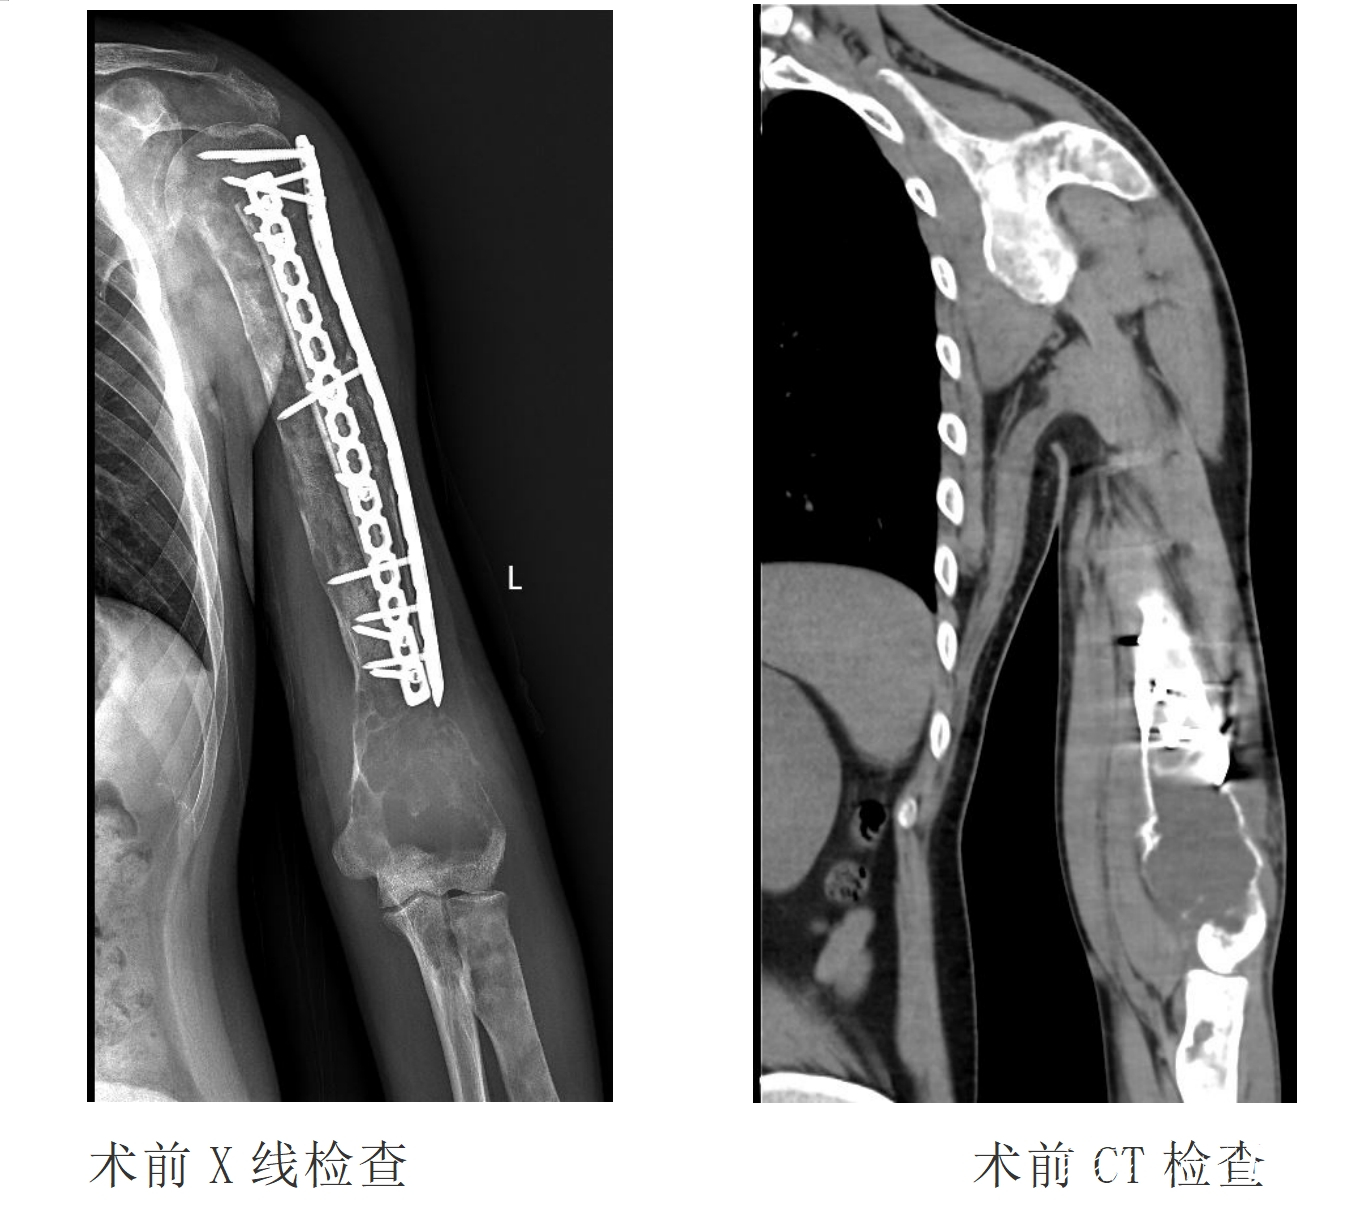

术前,骨科骨肿瘤团队为刘华精确测量了肱骨及肩、肘关节径线、角度,定制了人工假体等。手术当日,骨科骨肿瘤团队与麻醉科、手术室、影像科等多学科医护人员携手合作,历经3个小时,成功为刘华完成了3D打印仿生型全肱骨置换手术,术中有效重建了伸肌群及屈肌群。

据贵医附院骨科骨肿瘤团队介绍,全肱骨切除本身工程浩大,此次手术由于病灶范围较大,已经突破骨骼、侵润周围软组织,完整切除有相当难度。而且肱骨周围遍布重要神经、血管,不慎损伤后会造成患肢血液运输和循环及功能严重障碍,需要手术实施者非常小心,逐一妥善分离。为保证功能恢复,全肱骨切除后,还需要进行繁琐的重建程序。尤其要把握好假体放置的各种角度、各组肌腱止点恰当牢固的重建、假体长度的精细调整,以满足术后患肢的功能得到最大程度的恢复。